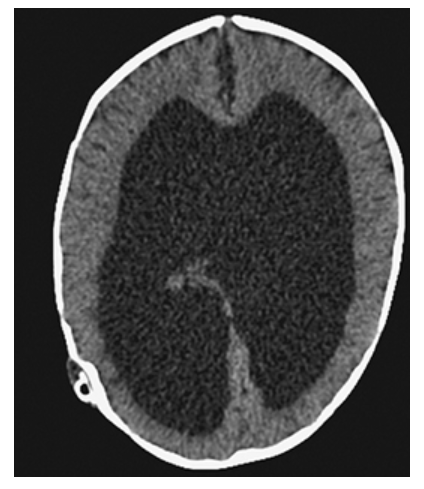

Hydrocephalus. Axial NECT shows markedly dilated lateral ventricles.